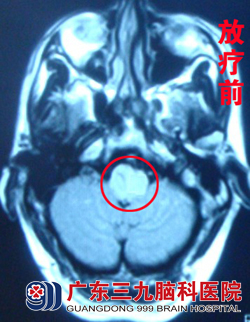

为求进一步治疗,邓先生于3月25日来到我院神经内科求进一步治疗,入院行头颅MRI+MRA检查见延髓、左侧小脑半球、桥脑背侧强化灶范围较前明显,提示肿瘤的可能性较大,邀请肿瘤综合治疗中心 蔡林波主任会诊,波普分析示Cho峰明显升高,提示恶性肿瘤可能性较大,遂于4月初转入肿瘤综合治疗中心进一步治疗。www.999brain.com

蔡林波主任查看其病情后,建议其首先予以手术探查,做活检以明确病理。但家属表示不愿意承担手术风险,选择直接行放化疗。4月9日,邓先生开始接受适形放疗及同步化疗。治疗1个多月后,邓先生病情逐步好转,走路不稳、视物重影等症状消失。治疗结束后两个月复查头颅MR 见脑干病变范围较前缩小,查体无明显阳性体征,邓先生一般情况良好,无不适。